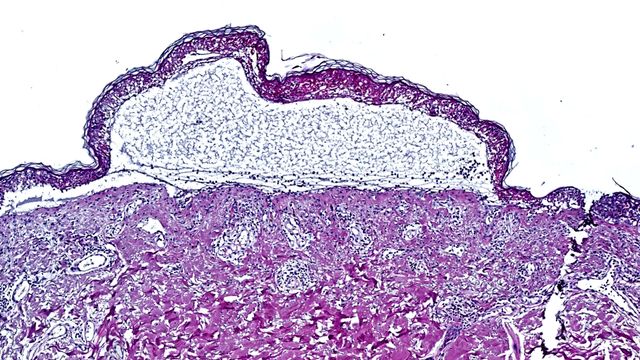

Targeting the JAK/STAT Pathway in Toxic Epidermal Necrolysis

Researchers have made a groundbreaking discovery that saves the lives of patients suffering from toxic epidermal necrolysis. Using innovative spatial proteomics the team identified the inflammatory JAK/STAT pathway as the main driver of disease.